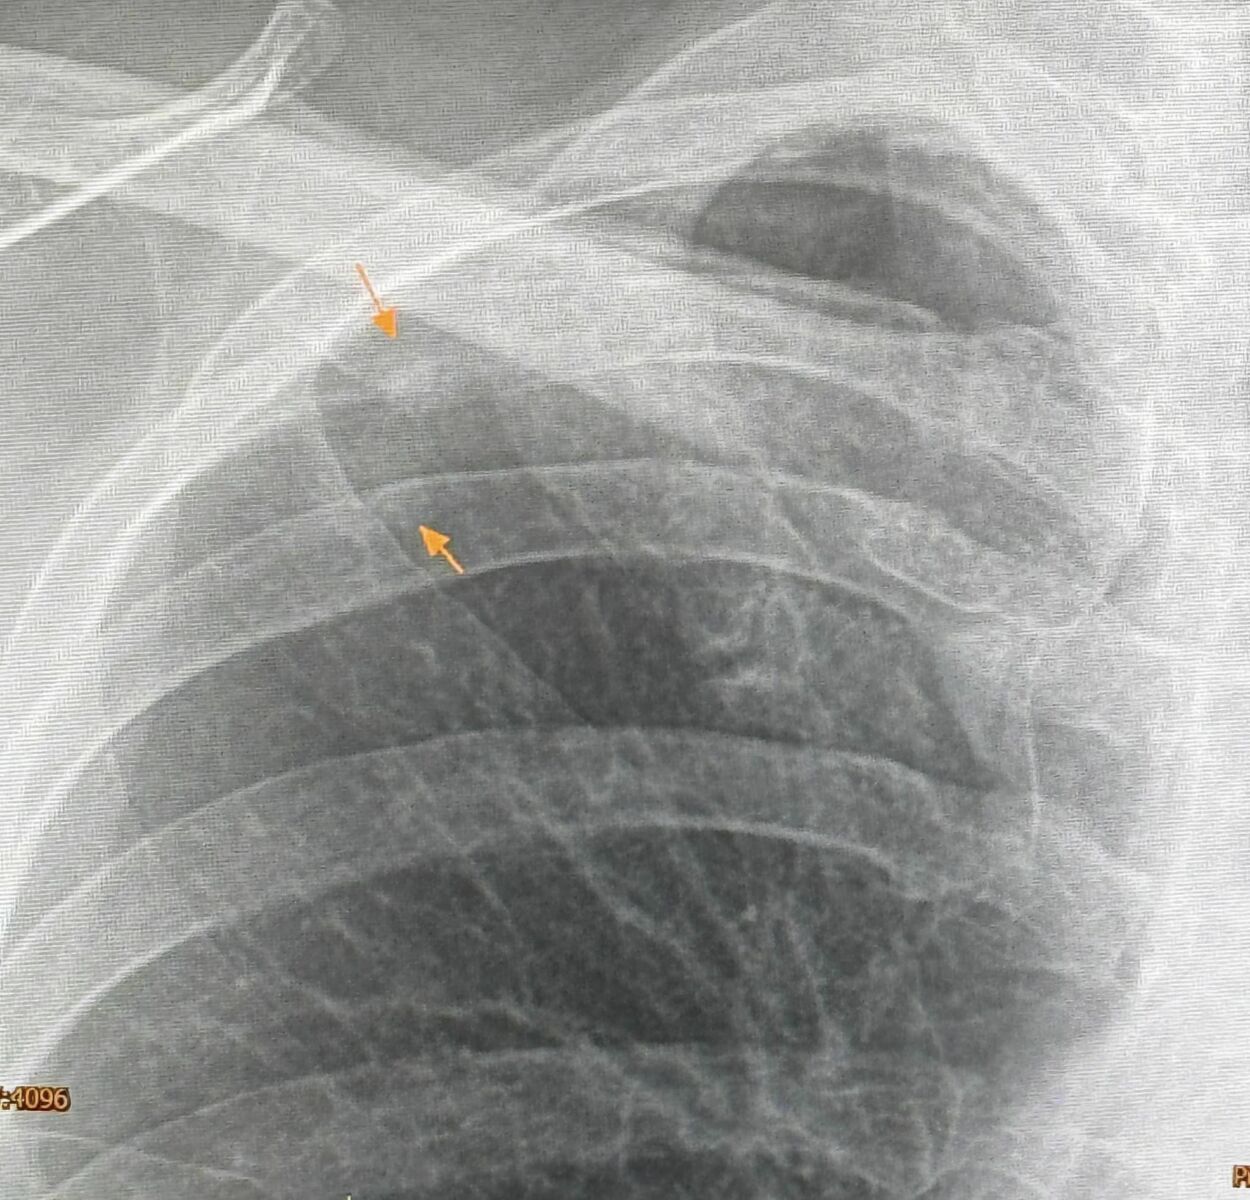

During a routine annual check-up on May 12, an X-ray revealed a new small mass in the upper lobe of her right lung. A previous X-ray from the year before was normal. A CT scan showed the mass measured 0.9 by 0.9 by 1.7 centimetres, with a cavity inside.